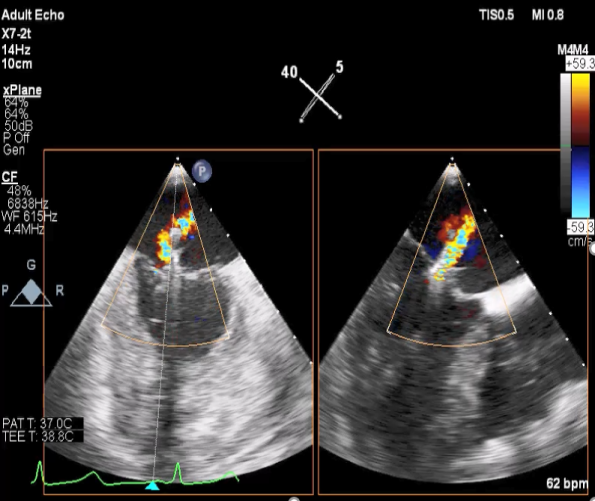

麻醉状态下TEE显示中大量返流MR:

患者麻醉方式采取全麻,建立静脉通路后,穿刺右侧股动脉以及股静脉,预埋ProGlide缝合器,冠脉造影复查提示支架通常。TEE超声指导下经房间隔穿刺后进入左房,送入鞘管,MitraClip调整后顺利到达二尖瓣目标位置,后在X线及食道超声辅助下,使用1枚XTR二尖瓣夹准确夹合二尖瓣A2-P2区,超声即刻测反流面积明显减少,LVOT切面,四腔心切面以及3D下证实夹合组织充分,患者收缩压由术前的108/62mmHg上升至130/72mmHg,左心房压力显著减低,肺静脉多普勒波形由反向恢复正常。手术顺利结束,安返普通病房。

二尖瓣联合部切面引导XTR夹子转向病变区域并逐渐进入左室

XTR夹子到达病变区域捕获瓣叶并逐渐夹闭

XTR夹子释放,返流明显减少